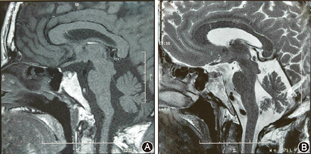

垂体MRI检查(图3):矢状位垂体稍饱满,局部见一团块样信号影,大小约0.9 cm×0.5 cm,T1WI高信号,T2WI呈相对低信号影,考虑垂体微腺瘤并出血。

A.T1像矢状位垂体稍饱满,局部见一团块样高信号影,大小约0.9 cm×0.5 cm;B.T2像呈相对低信号影